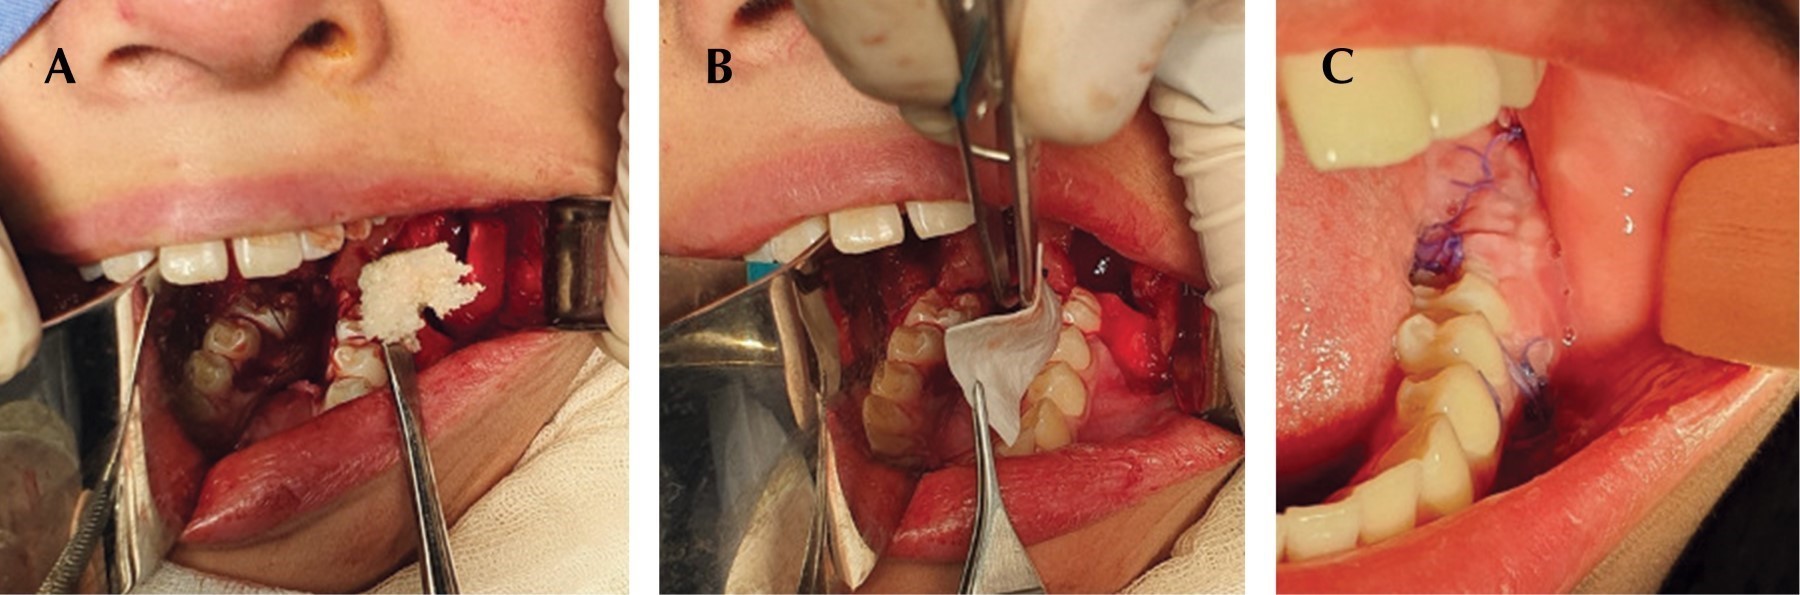

Bajo anestesia general y con intubación orotraqueal, se realizó la resección quirúrgica conservadora de la lesión, con curetaje en todo el lecho quirúrgico y odontectomía del segundo molar inferior izquierdo. No se observó comunicación al conducto dentario inferior ni perforación de las corticales óseas en el transoperatorio (Figura 3).

Se colocaron suturas en la periferia de la herida, simulando una marsupialización y se introdujo en el lecho quirúrgico injerto óseo y membrana para la correcta regeneración de tejidos y así obtener una mayor facilidad en la parte de rehabilitación con implante.

Figura 3